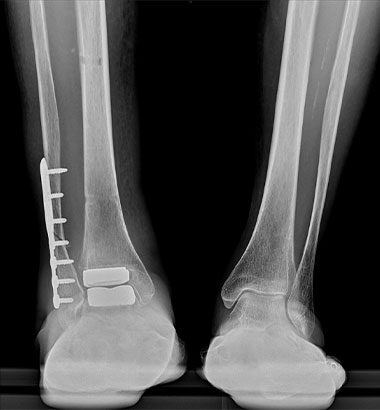

足くびの外側から手術を行う外側侵入型の人工足関節です。

この手術では、まず腓骨を骨切りし、足くびの外側からアプローチします。そこから脛骨と距骨で構成される「距腿関節(きょたいかんせつ)」の表面を削り、人工関節を設置します。特に、距腿関節のみが変形しており、距骨自体のつぶれや他の関節の障害がない方に向いています。人工関節は金属と医療用の特殊な素材でできています。

術前

術後